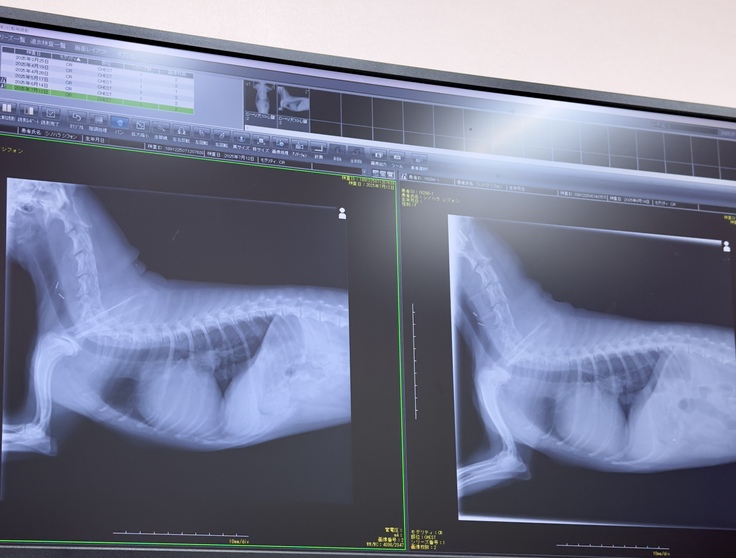

術後2ヶ月半…検診に行って来ました!

7月12日前回から4週間目、術後2ヶ月半となりました。

今日は検診日…猛暑の中シフォン頑張って検診に行って来ました。

結果は良好で手術をした左心房の方は完璧とのこと!

右心房の方の肥大と三尖弁の逆流が気になりそちらも検査して頂きました。

心臓自体の大きさは前回の6月14日の時と変わらずで右心房の肥大も然程なく三尖弁の不具合も今のところ気にならないとのこと。

血栓もなく順調だと言われ安心しました。

お薬は前回と同じくアピナック2分の1錠とクロシドグレル4分の1錠を1日1回が30日分処方されました。

こちらを飲み切ってから更に1ヶ月経過した9月の半ばに再度検診に行く予定です。